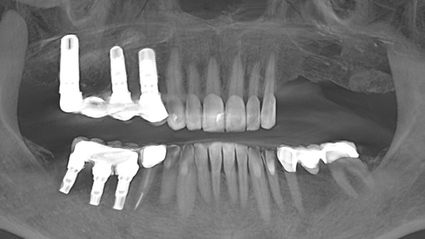

Vor